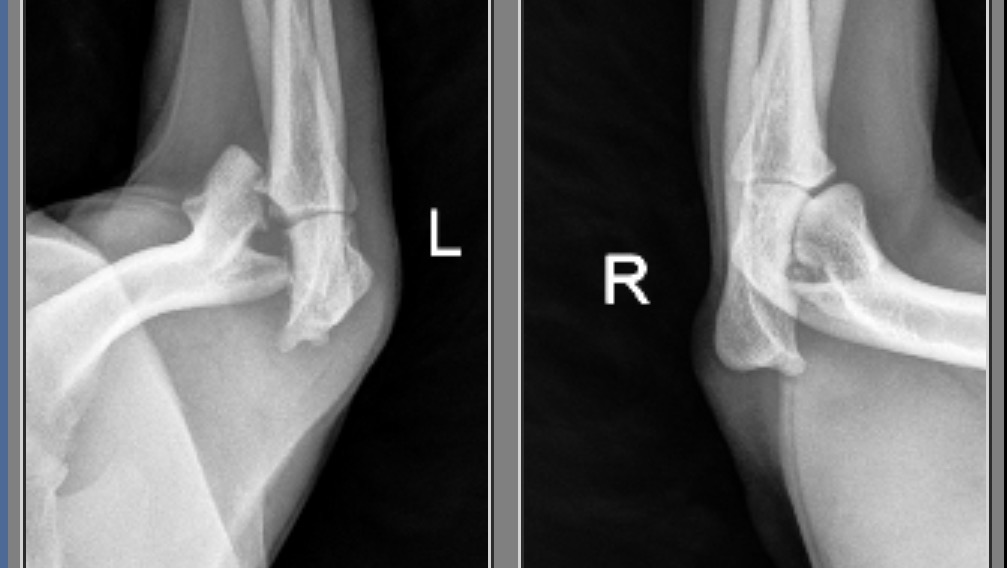

Hello, my name is Alaina Moncrief, and I'm reaching out for help on behalf of my beloved dog, April. Recently, April suffered a severe front humeral condyle fracture, which requires emergency surgery to repair. This injury is both painful and urgent, and without surgery, April’s quality of life will be significantly compromised.